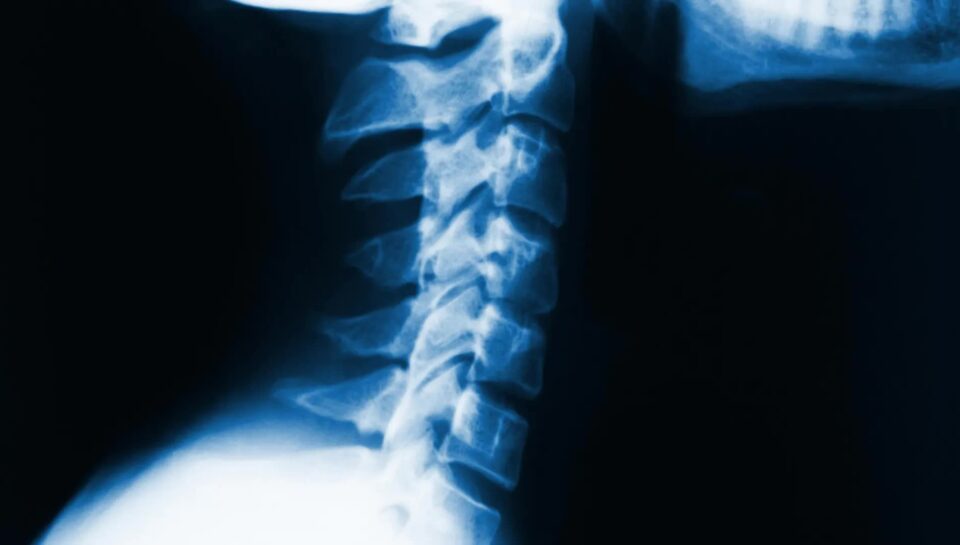

Humbja e lordozës cervikale, e njohur ndryshe si sheshtëzim i qafës, ndodh kur harku natyror i pjesës së sipërme të shtyllës kurrizore zhduket ose reduktohet. Kjo gjendje mund të shkaktojë dhimbje qafe, shpatullash, mpirje në krahë dhe kufizim të lëvizshmërisë. Në Fizio Tirana, ne ofrojmë trajtime profesionale dhe të personalizuara fizioterapie për të rikthyer funksionin normal të qafës, përmirësuar qëndrimin dhe reduktuar simptomat.

Fizioterapia është një nga metodat më të efektshme për trajtimin e humbjes së lordozës cervikale, duke rikthyer funksionin dhe fleksibilitetin e qafës. Në klinikën tonë, çdo pacient merr një plan trajtimi të personalizuar që mund të përfshijë: